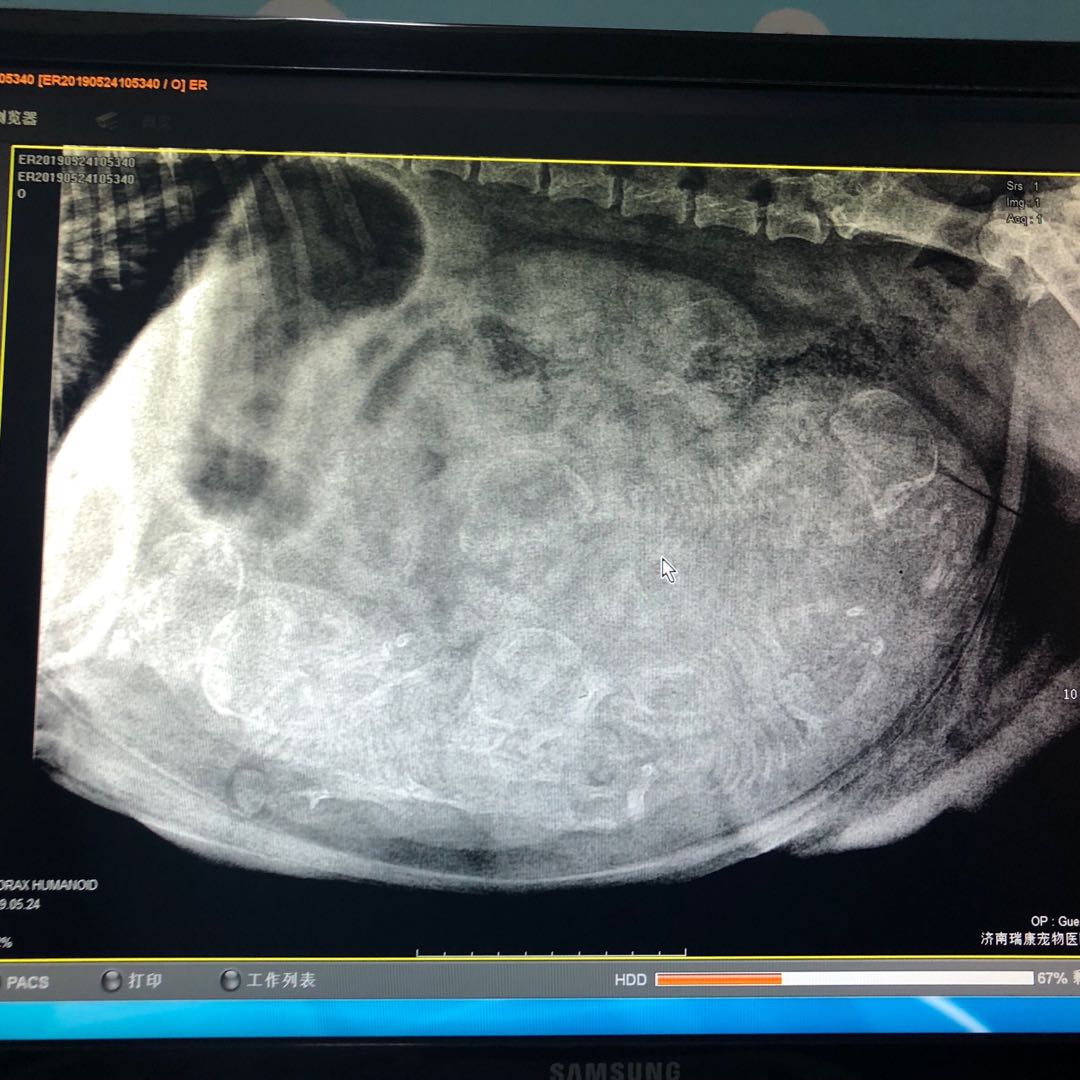

众所周知,英国斗牛犬自己是生不出来的,需要剖腹产。眼看巴莎的预产期一天天临近,但它到处趴窝等明显生产特征。我揣揣不安的等到巴莎怀孕第62天,去医院为它做了胎心检测,当医生说可以剖了时,我便见证了巴莎成为六胎英雄母亲的全过程。

剖腹产拍片